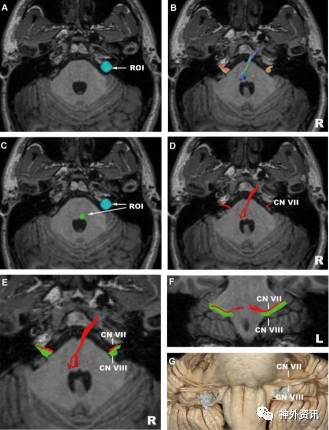

图8. 面-前庭蜗神经。A.ROI置于面神经与前庭蜗神经复合束,主要位于内听道中心;B.面-前庭蜗神经复合束(轴向位),可以重建出所有脑池段面-前庭蜗神经复合束及桥脑以上纤维束;C.ROI置于面神经,位于面神经丘毗邻处;D.面神经(轴向位);E.面神经和前庭蜗神经(轴向位),红色:面神经,绿色:前庭蜗神经;F.面神经和前庭蜗神经(冠状位);G:对应F图的解剖图(正面观)。